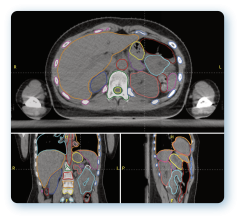

December 11, 2008 - The first patient to be treated clinically with a new treatment planning system for proton radiation therapy developed by RaySearch took place at Uppsala University Hospital in Sweden.

The system is integrated in the Oncentra MasterPlan treatment planning system from RaySearch's partner Nucletron. The University Hospital treats more than 100 cancer patients annually with proton therapy at the The Svedberg Laboratory and the system will be used for all proton treatments in the future.

"The new treatment planning system saves substantial time with its user-friendly tools providing us with various optimization alternatives and the possibilities of making fine adjustments. The dose calculations are exact and optimized to the clinical reality. In addition to the concise presentation of treatment plan data, filter and field shapes are visualized graphically in a clear and pleasant manner," said Christina Vallhagen Dahlgren, senior hospital physicist, proton therapy at the University Hospital.

Proton therapy is one of RaySearch's prioritized development areas and the company is participating in discussions regarding a number of business opportunities in the field. For example, RaySearch is working actively with its partner Nucletron on four tenders.